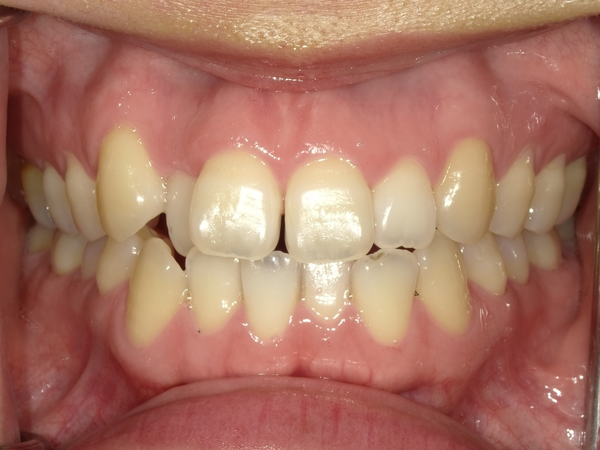

●ご相談内容:歯がガタガタしてる●矯正の種類:マウスピース型矯正「インビザライン」●治療期間:26週間●治療費用:66万円(税込)